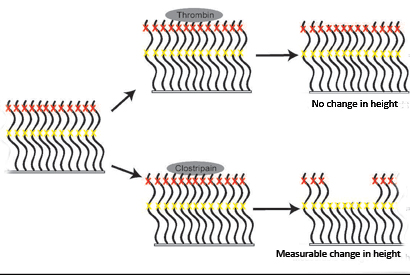

Bioinspired coating for medical devices avoids clotting and suppresses bacterial infection

Repels blood and bacteria, including biofilms